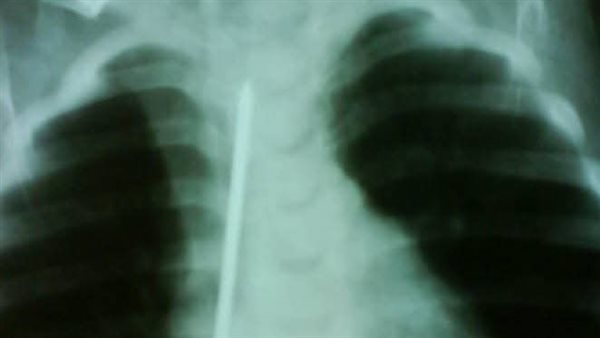

وأضاف قائلًا: "كانت الطفلة في حالة طبيعية تمامًا، تتنفس بشكل جيد ولا تعاني من أي صعوبة في البلع، لكن أمام إصرار الأم على أنها بحثت جيدًا في المنزل، قررت إجراء أشعة على صدر الطفلة، لتظهر المفاجأة الصادمة مسمار طويل يمتد بطول القفص الصدري تقريبًا."